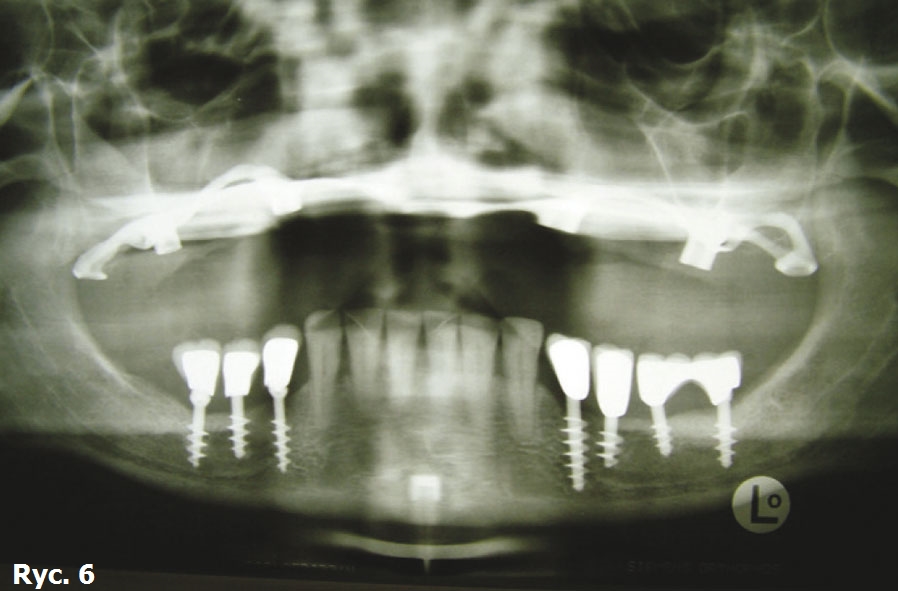

Pacjentka wyraża zgodę na zabieg chirurgiczny, polegający na wprowadzeniu wszczepów podokostnowych, zdając sobie sprawę, że jest to ostatnia deska ratunku, umożliwiająca stabilne zakotwiczenie protezy wspartej na wszczepach. Po zabiegu implantacji dwie oddzielne siatki podokostnowe (ryc. 3) zostaną ze sobą połączone (ryc. 4). Podniesiony płat śluzówkowo okostnowy (ryc. 5) ukazuje zgodność anatomii tkanki kostnej z modelem stereolitograficznym. Pozabiegowe zdjęcie pantomograficzne (ryc. 6) obrazuje idealne połączenie między dwiema siatkami, umieszczonymi precyzyjnie na swoim miejscu. Mezostruktura (ryc. 7) jest odpowiednim podparciem dla docelowej protezy typu „U” (ryc. 8).